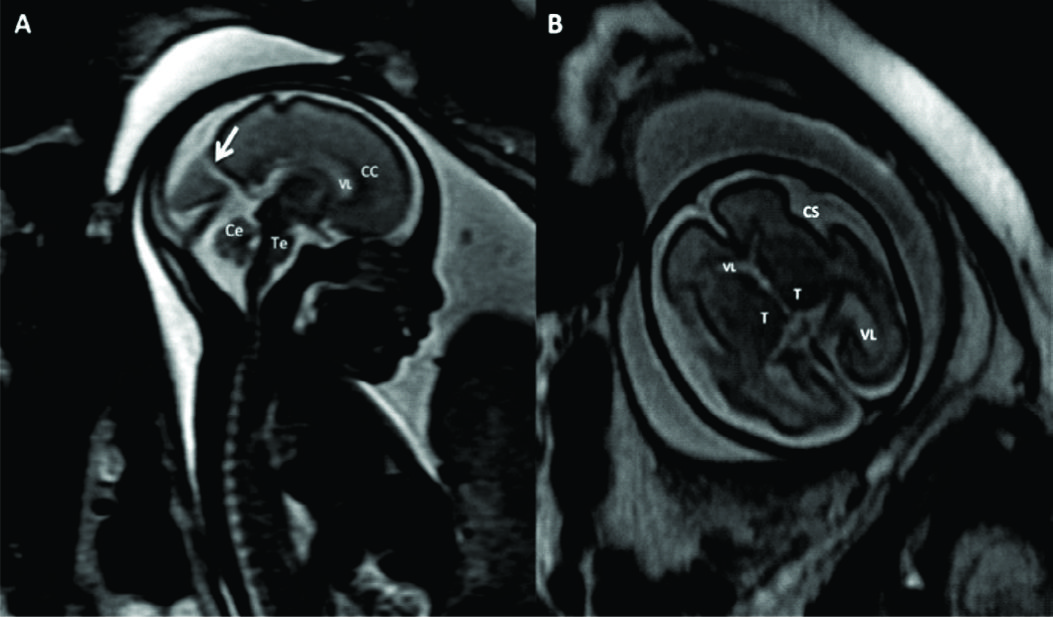

Figura 4

RM Fetal Hidrocefalia por Estenosis del acueducto.

Se presentan 2 casos de fetos con hidrocefalia (HCF) por estenosis del acueducto. El primer caso se presenta con HCF leve/moderada (A sagital y B axial) donde puede observarse la dilatación ventricular supra-tentorial con IV ventrículo normal lo que orienta al diagnóstico de estenosis del acueducto.

En C se muestra imagen sagital del 2º caso con HCF severa y ausencia de señal en el acueducto de Sylvio lo que orienta al diagnóstico (è). AV: Atrio ventricular

CC: cuerpo calloso

Te: Tronco encefálico

Ce: Cerebelo